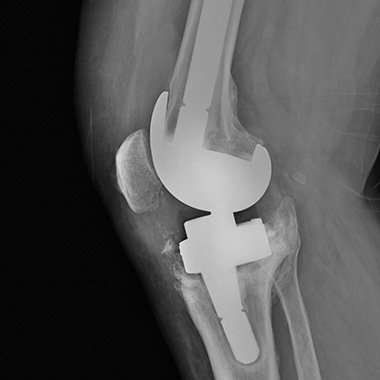

Endoproteza stawu kolanowego

Endoprotezoplastyka stawu kolanowego to skuteczna metoda leczenia zaawansowanej choroby zwyrodnieniowej kolana. Zabieg polega na chirurgicznym usunięciu uszkodzonych powierzchni stawowych i ich zastąpieniu nowoczesnym implantem – całkowitym lub częściowym – który przywraca funkcję stawu, poprawia jego stabilność i eliminuje ból. Leczenie to jest przeznaczone dla pacjentów z silnymi dolegliwościami bólowymi, ograniczeniem ruchomości, sztywnością kolana oraz brakiem efektów leczenia zachowawczego.

Endoprotezoplastyka kolana wykonywana jest z użyciem wysokiej jakości implantów, które dobieram indywidualnie do budowy anatomicznej pacjenta oraz jego aktywności życiowej. Nowoczesna technika operacyjna umożliwia precyzyjne ustawienie osi kończyny dolnej oraz uzyskanie stabilnego i trwałego efektu leczenia.